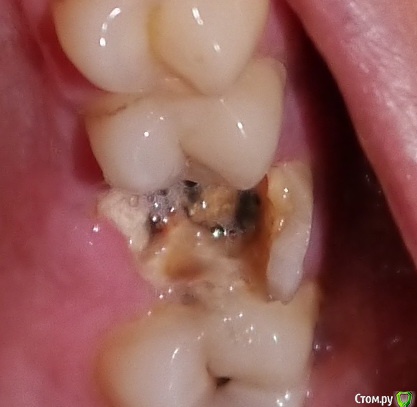

wainerrr Опубликовано 16 апреля, 2016 Поделиться Опубликовано 16 апреля, 2016 Здравствуйте! 3 дня назад выпала пломба, разрушился зуб, корни остались. Болевые ощущения пока не испытываю.Хотелось бы узнать стоит ли удалять сразу либо:1. перелечить корни, запломбировать и оставить (насколько это надежно и долго продержится ? )Как мне объяснили при выдаче снимка - залечен один корень и тот не до конца, остальные не тронуты, вокруг корня есть воспалениеВ августе 2015г. в этом месте был периодонтит вокруг корня, принимал цифран СТ500, прошло2. Есть ли он сейчас периодонтит (судя по снимкам)?3. До лечения нужно решить вопрос с периодонтитом?4. Как лучше перелечить:1) просто запломбировать корни ?2) запломбировать корни и установить в корни анкерные штифты (или стекловолоконные) на которые наростить пломбу ?3) запломбировать корни и установить в корни разборную штифтовую вкладку на которую наростить пломбу ? Каковы риски дальнейших воспалительных процессов при перелечивании ? 5. На зубе, находящимся рядом с разрушенным один врач глядя на потемнение сказал, что надо лечить, дугой сказал,что зуб в порядке -Ваше мнение? Спасибо ! Ссылка на комментарий

Ker Опубликовано 16 апреля, 2016 Поделиться Опубликовано 16 апреля, 2016 (изменено) Корни просто удалить, периодонтит есть и не маленький, соседний зуб лечить 100%. Изменено 16 апреля, 2016 пользователем Ker Ссылка на комментарий